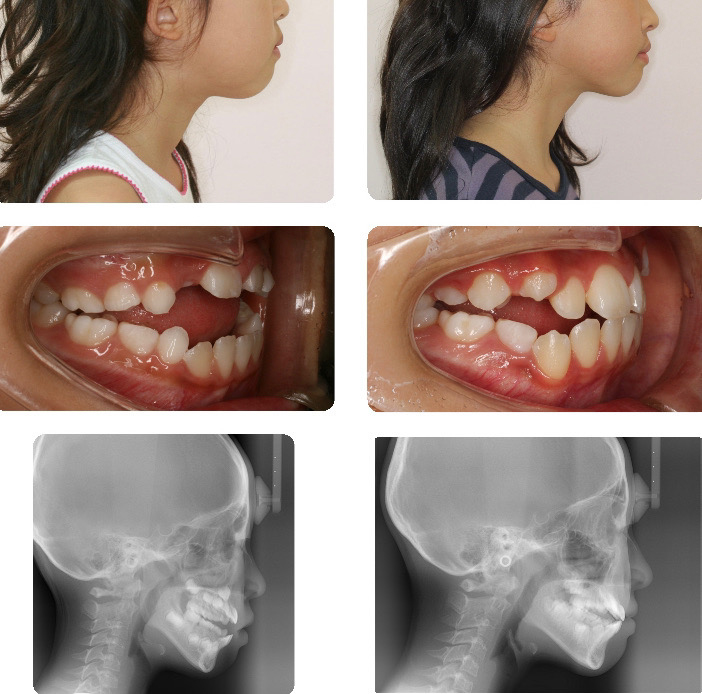

乳歯列反対咬合

乳歯列の反対咬合で特に左右的偏位がある場合には、早期の咬み合わせの改善が望まれます。

乳歯列時の咬み合わせの改善により、永久前歯が萌出した後の正常な咬み合わせが期待できます。

本症例も前歯が永久歯に生え替わったあと、正常被蓋になりました。

ただ生え替わりにスペースがやや不足していたため、歯列の拡大を行いました。